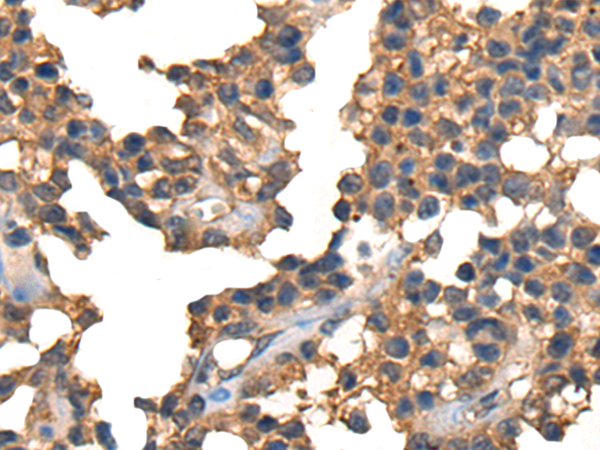

ELISA, IHC |

IHC positive control: |

Human liver cancer and Human ovarian cancer |

IHC Recommend dilution: |

25-100 |